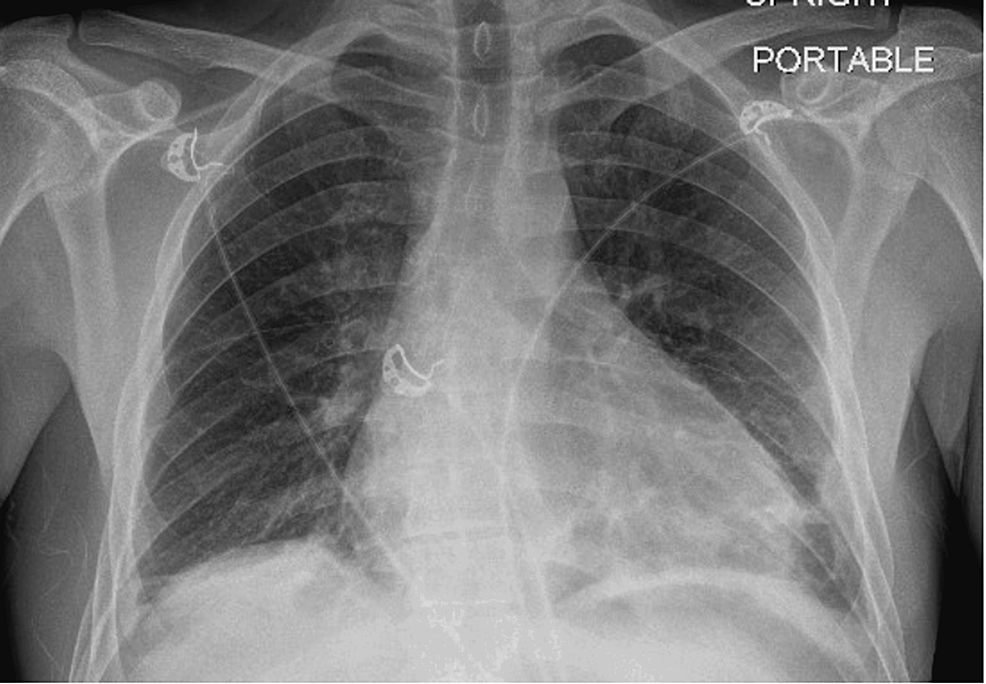

Ultimately, a respiratory review was warranted given the patient’s history with pulmonary sarcoidosis and a thorough evaluation sought the need for multiple investigations including a CT sinus, CT thorax, and bronchoalveolar lavage to investigate a preliminary diagnosis of EGPA. In addition, he was commenced on 500 mg of IV methylprednisolone on a once-daily basis for three days followed by a weaning course of prednisolone starting at 60 mg and Septrin as prophylaxis. CT thorax revealed small bilateral pleural effusions, bibasal atelectasis, slightly prominent bilateral hilar, and perihilar lymphadenopathy consistent with sarcoidosis, and a very large 3 cm pericardial effusion, which warranted urgent cardiothoracic input. The patient was thereby admitted to the coronary care unit and started on colchicine. Pericardiocentesis was not performed given the posterior location of the effusion and a cardiac MRI was booked to investigate for any fibrosis/sarcoid following resolution of the effusion. CT sinus revealed a hypoplastic left maxillary sinus with longstanding opacification and bronchoalveolar lavage fluid was shown to have >5% eosinophils. The patient had 22 chest X-rays and three CT thorax scans performed from 2014 to 2022. All chest radiology was reviewed to identify any evidence of migratory infiltrates. Temporal proof showing infiltrates being migratory was identified (Figures 8, 9) with the addition of altering small pleural effusions seen bilaterally (a feature that is evident in 50% of patients with EGPA) [6].